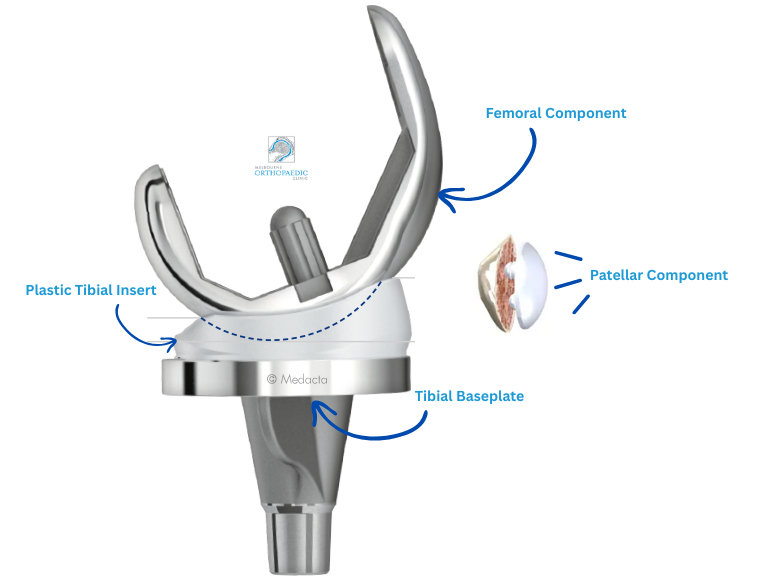

The knee replacement implant components

During a total knee replacement procedure, damaged bone and cartilage are replaced with prosthetic components that mimic the function of your natural joint. These components are carefully selected to restore mobility, stability, and comfort, tailored to your unique anatomy and lifestyle needs.

Knowing the basic structure and function of a knee implant can help you better understand what’s involved in your surgery and what contributes to the success of the outcome.

The femoral component is made of metal (usually a cobalt-chromium or titanium alloy) and is shaped to match the contours of the end of your thigh bone (femur). It curves around the front of the knee and fits into a groove that allows your kneecap (patella) to glide smoothly as the knee moves. This component bears much of the load during walking, squatting, or bending and must be precisely aligned to allow for smooth flexion and extension of the knee.

The tibial component consists of two parts:

Tibial baseplate: A metal platform fixed to the top of your shin bone (tibia) using either bone cement or a press-fit technique.

Tibial insert: A high-grade plastic spacer (made of ultra-high-molecular-weight polyethylene) that sits atop the baseplate.

This plastic insert functions like your knee’s natural cartilage. It cushions the joint, absorbs shock, and allows the femoral component to glide smoothly over the tibial surface. Modern inserts are engineered to be wear-resistant and may include antioxidant-enhanced materials such as Vitamin E to improve durability. In some cases, if only the plastic insert wears out over time, it can be replaced without disturbing the metal implants.

Not all knee replacements require resurfacing of the patella (kneecap), but when it is involved, a small plastic dome is attached to the underside of your kneecap. This enables it to move more smoothly over the femoral component during knee bending and straightening.

Implant materials and durability

Knee implants are typically made from a combination of cobalt-chrome or titanium alloys, and high-grade polyethylene (plastic). These materials are biocompatible, which means they are designed to function safely within your body. Modern implant designs and materials aim to reduce wear and extend the life of the replacement. Your surgeon may select either a fixed bearing or mobile bearing implant design

The choice of implant materials, sizes, and design features is determined by several factors including your bone quality, activity level, and the alignment of your knee. During pre-operative planning, imaging such as X-rays, CT, or MRI scans help your surgeon select and position the components to match your natural anatomy.

At Melbourne Orthopaedic Clinic, your surgeon will select a prosthesis from a range of well-established implant systems known for their safety, performance, and long-term outcomes.

Fixed bearing designs have a polyethylene insert locked into the tibial baseplate. This is the most commonly used type and is suitable for many patients.

Mobile bearing designs allow some movement between the insert and the baseplate, which may offer better rotation for selected patients.